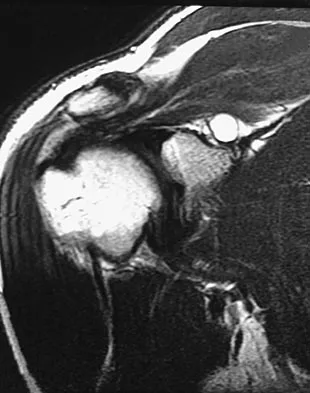

A 40-year-old right hand-dominant construction worker has had a 6-month history of aching left shoulder pain that is worse after working a long day. Examination reveals limited range of motion and good strength when compared to his asymptomatic right arm. He has not had any orthopaedic intervention to date. Radiographs are shown in Figures 43a and 43b. What is the most appropriate treatment?

Explanation